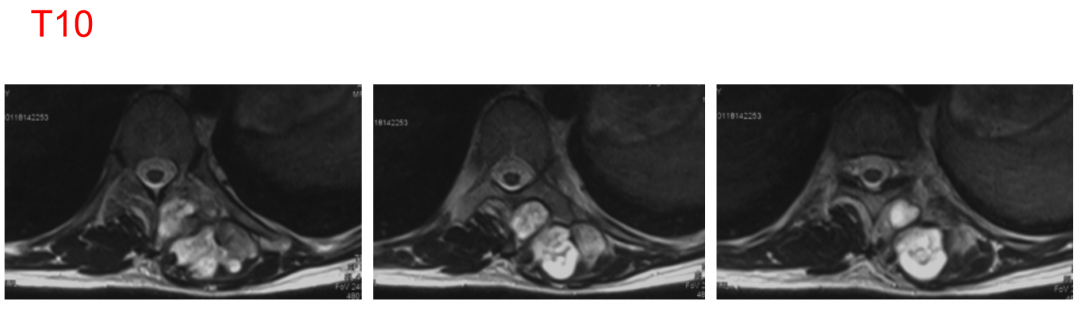

MR T2

MR +C

F, 34y

Left lateral back pain for half a year, aggravation for 3 months